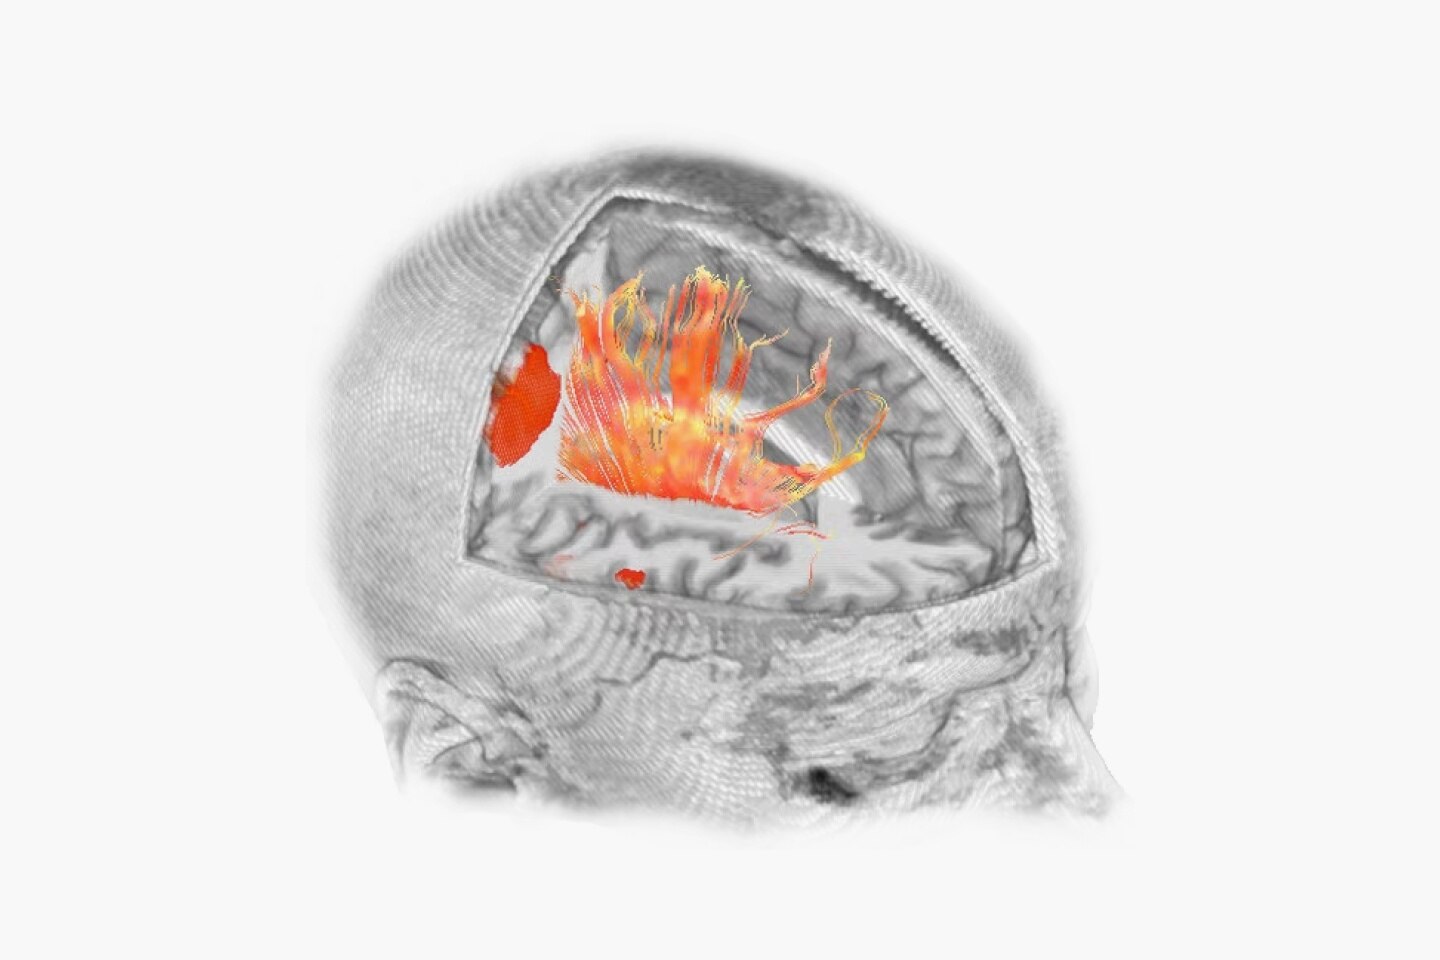

Imaging Technology

A resolution revolution.

The Voluson Signature 20 is a top performer. Powered by a progressive, highly flexible system architecture and coupled with Voluson’s advanced transducer technology migrated from our premium Expert series platform, take a big leap in image quality. With a new level of depth and clarity, accelerate your diagnostic capabilities so you can always deliver your most confident care.